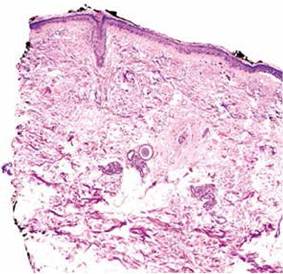

Se realizó biopsia cutánea incisional, cuyo estudio histopatológico fue concluyente con poroqueratosis actínica superficial diseminada, evidenciándose la presencia de una lámina cornoide característica(Figuras N° 3 y 4).

Figura N° 3. Tejido cutáneo con atrofia epidérmica, estrato basal con aumento de melanina y reacción de interfase vacuolar, dermis con elastosis solar difusa. Figura N°4. Se evidencia epidermis con paraqueratosis (lámina cornoide) dentro de una invaginación epidérmica, dermis con infiltrado infamatorio crónico.